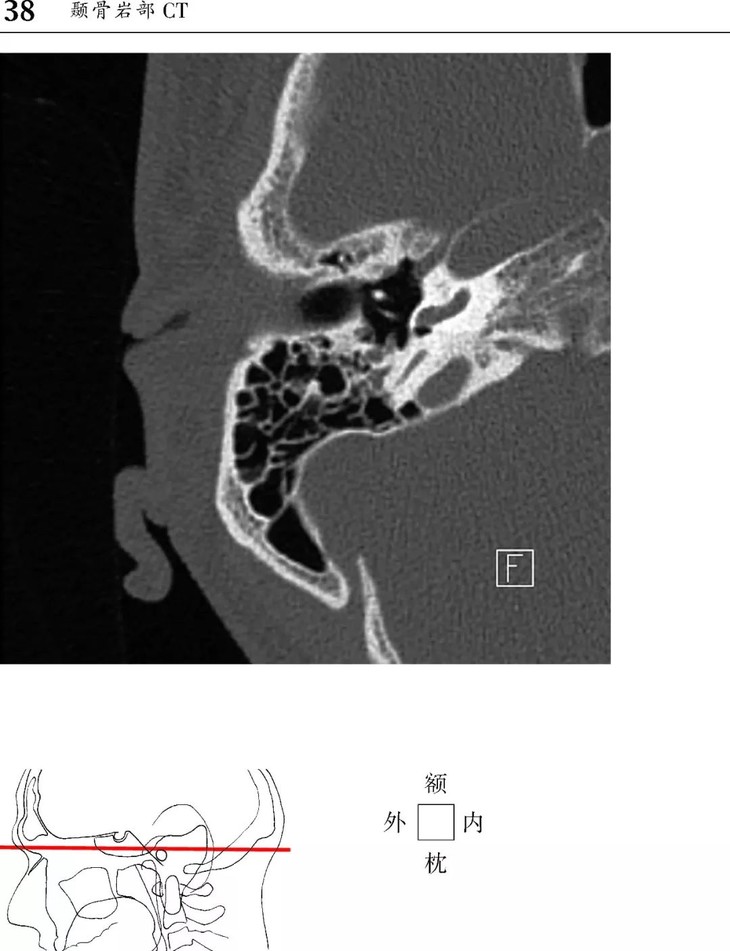

本书为断层解剖图谱,包括头颈部断层解剖,还包括脑部血管造影术,每一层面都包括精确的断层解剖和对应的彩色插图,左边页面为CT/MR图像,右边页面为对应的彩色手绘解剖示意图,便于学习和记忆!

1、版面采用教学式设计,2页为一个单元,左边页面为CT/MR图像,右边页面为对应的彩色手绘解剖示意图,并一一注明了解剖部位。

2、几百幅高清的CT/MR图片,对解剖结构显示更加清晰,其中许多图片都是采用最新的设备扫描的,如3.0T MRI,64层CT。

1、头部CT图像新增轴位和冠状位颞骨图像。